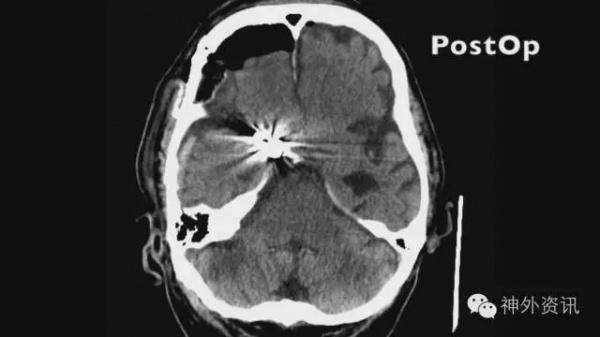

图16. 术后复查见脑组织无肿胀缺血。